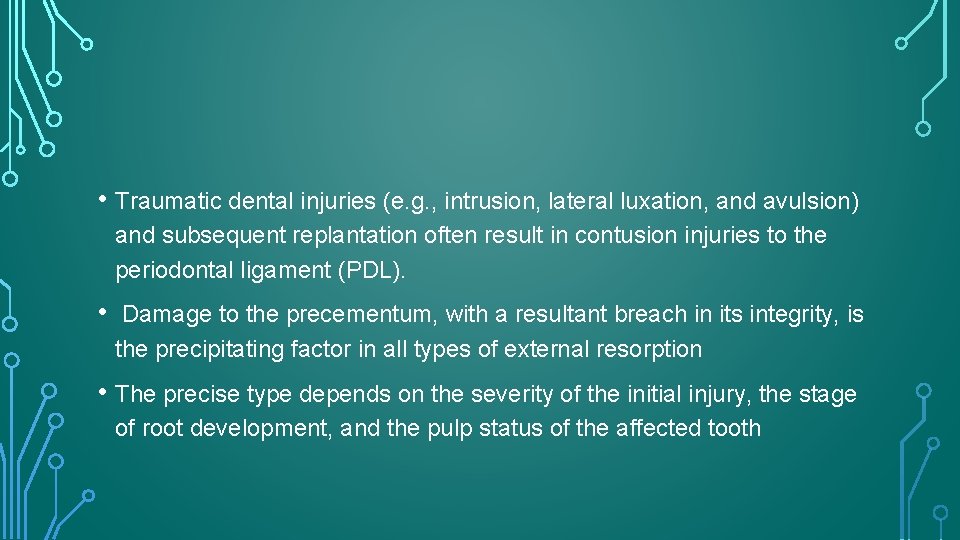

• Traumatic dental injuries (e. g. , intrusion, lateral luxation, and avulsion) and subsequent replantation often result in contusion injuries to the periodontal ligament (PDL). • Damage to the precementum, with a resultant breach in its integrity, is the precipitating factor in all types of external resorption • The precise type depends on the severity of the initial injury, the stage of root development, and the pulp status of the affected tooth